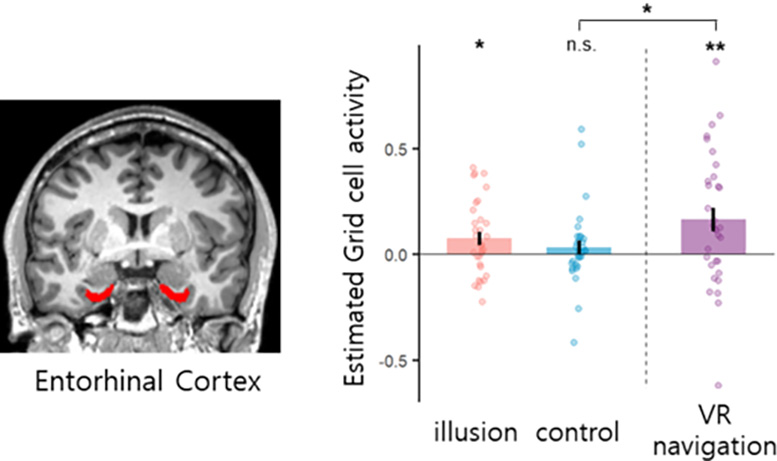

פעילות תאי רשת בקליפת המוח האנטורינל במהלך תנאי משימה שונים. קרדיט: מכון קוריאה למדע וטכנולוגיה

כתוצאה מכך, הצוות הוכיח לראשונה ששינויים קוגניטיביים גרידא במיקומים מגנטיים שינויים במיקום עצמי הזויים הנגרמים על ידי גירוי גוף רב חושי, ללא כל שינויים ברמזים הסביבתיים החזותיים, מעוררים פעילויות מקבילות של תאי רשת אנושיים.

זהו המחקר הקליני הראשון שהוכיח שגירויים גופניים רב-חושיים לבדם יכולים לעורר פעילויות של תאי רשת, ללא כל סוג של ניווט (לא פעיל ולא מדומיין) וללא שינוי בפרספקטיבה החזותית. הוא מראה כי קואורדינטות GPS במוח האנושי מגיבות לא רק למיקום הפיזי של הגוף אלא גם למידע על מיקום המבוסס על פעילויות והתנסויות קוגניטיביות שונות, מה שמעלה את האפשרות לאבחון אובייקטיבי של תסמינים הזויים באמצעות ניתוח תמונת מוח. הממצאים צפויים גם לתרום לפיתוח טיפולים חדשים על ידי מתן מטרות לטיפול בחולים הסובלים מתסמינים הזויים כגון חוויה חוץ-גופית.